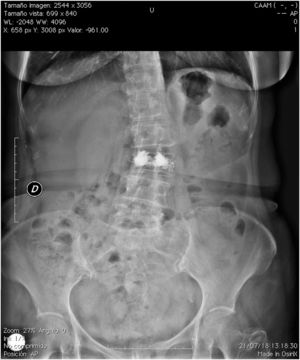

A 65-year-old female assessed for low back pain with a history of CT-guided percutaneous vertebroplasty 4 years previously secondary to vertebral fracture due to osteoporosis. As mentioned by the patient, the procedure was performed without complications and from it she achieved partial improvement of pain. On questioning she denied any respiratory symptoms. On physical examination the vital signs were normal, with 99% ambient air oxygen saturation. In the thoracic assessment the heart sounds were rhythmic, without murmurs, and the lung fields were not altered. Lumbar spine ranges of motion were diminished and there was pain on active and passive movement. Lumbar spine radiography showed scoliosis, as well as volume loss and the presence of radiopaque material at L3 (Fig. 1). Chest radiography showed the presence of radio-opaque material in right-dominant pulmonary vascular distribution (Fig. 2). Vertebral fracture is the most common complication of osteoporosis.1 In some patients vertebroplasty is used to reduce pain.2 This procedure involves the injection of cement to stabilise the anterior spine. Leakage of material has been reported in 30%–65% of patients. The risk factors described for this complication are: intravertebral fissure, cortical disruption and procedure-related factors (viscosity of the cement and volume of cement injected).3,4 It is considered that overfill of the vertebral body or inadvertent puncture into the radiated veins will facilitate the migration of cement into the perivertebral venous plexus, to pass through the hemiazygous vein, the azygous vein and flow into the inferior vena cava, which is where polymerisation of the material and embolism will occur.2 Most patients have reported asymptomatic side effects. In cases of pulmonary embolism, it has been reported that 26% will be asymptomatic5 and in <1% of cases will present some symptoms.6,7 The patient was sent to rehabilitation and treated with analgesics, with a good short-term outcome.